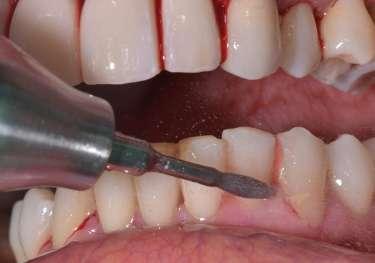

Trattamento di carie cervicale di elemento 1.5 con laser a Erbio

1 2

Paziente femmina, 38 anni che presenta carie cervicale dell’elemento 1.5. Gengivectomia con manipolo angolato, tip in zaffiro con diametro di 400 μm, lunghezza 12 mm, 2.4 W, 20 Hz, 120 mJ E per impulso, potenza di picco 750 W, densità di potenza media 659 W/cm2, densità di potenza di picco 205,860 W/cm2, energia totale 432 J, larghezza impulso 160 μs, distanza tip-tessuto 1 mm, 50% acqua, 50% aria, tempo totale di trafamento 180 sec. Impostazioni dello smalto: manipolo angolato, tip in zaffiro diametro 800 μm, lunghezza 12 mm, totale energia 810 J, ampiezza dell’impulso 160 μs, distanza tip-tessuto 1 mm, 100% acqua, 70% aria, tempo di trafamento totale 180 sec.

3 5 6

Impostazioni dentina e smear layer: tip in zaffiro con diametro 800 μm, lunghezza 12 mm, 3.3 W, 20 Hz, 165 mJ, potenza di picco 1031 W, densità di potenza media 360 W/cm2, densità di potenza di picco 112,346 W/cm2, energia totale 594 J, ampiezza dell’impulso 160 μs, distanza tip-tessuto 1 mm, 100% acqua (18 ml/min), 70% aria, tempo di trafamento totale 120 sec.

Fig. 1 – Cavità su 1.5 Fig. 2 – Particolare della cavità del dente 1.5 Fig. 3 – Preparazione Laser Er:YAG Pluser con lunghezza d’onda di 2940 nm di LAMBDA DoctorSmile, Italia. Fig. 4 – Particolare della cavità dopo gengivectomia Fig. 5 – Particolare della cavità completata dopo la preparazione della dentina Fig. 6 – Restauro finale in composito (Asteria Tokuyama, Japan)